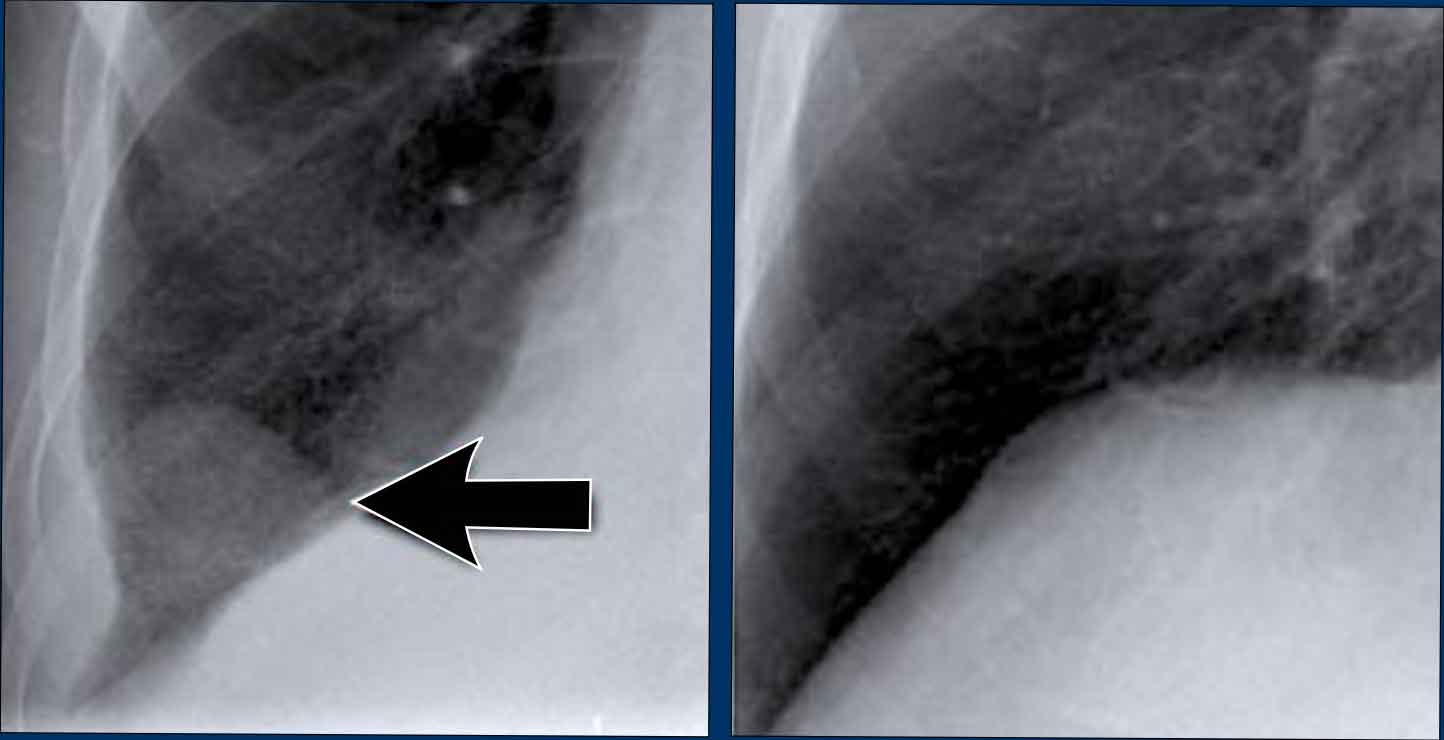

1. No silhouette sign in a consolidation located in the left lower lobe (blue arrow). 2. Silhouette sign in a consolidation in the lingula lobe (yellow arrow).

Silhouette sign

The silhouette sign refers to the loss of the normal border between structures of different radiographic densities, most commonly air-filled lung adjacent to soft tissue structures like the heart or diaphragm.

This sign is crucial for detecting subtle pathology and localizing lesions within the thorax.

Illustration of the Silhouette Sign

- No Silhouette Sign (Blue Arrow)- The left ventricle, located anteriorly, is normally bordered by air-filled lingula of the left upper lobe.

- If a consolidation occurs in the left lower lobe (posterior), the interface between the lingula and the heart remains intact, and the left heart border is preserved.

- Positive Silhouette Sign (Yellow Arrow)- When consolidation is present in the lingula, which directly abuts the left heart border, the silhouette of the left ventricle becomes obscured.

- This indicates the pathology is located anteriorly in the chest.

Silhouette Sign – Examples

Case 1: PA View

- The left heart border is obscured on the PA radiograph.

- Without even reviewing the lateral view, this finding localizes the pathology to the anterior segment of the left lung, likely the lingula.

- Diagnosis: Lobar pneumonia due to Streptococcus pneumoniae.

Case 2: PA View

- A consolidation is visible in the left lower lobe (yellow arrow).

- The left heart border remains well-defined with a normal silhouette (blue arrow), indicating the lesion is posterior, not involving the lingula.